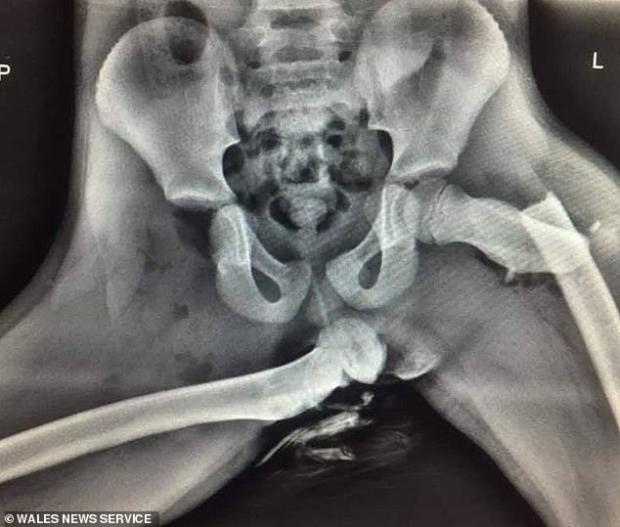

Radiografia unei tinere care a trecut printr-o astfel de situație arată cât de devastatoare sunt fracturile la nivelul șoldului, în cazul unui impact frontal.

În imagine se văd oase zdrobite și dislocate, fracturi ce vor fi cu greu vindecate.

”Femeia din radiografie a supraviețuit, însă rănile suferite de ea i-au schimbat definitiv viața. Dacă vedeți că pasagerul din dreapta face același lucru, opriți mașina și arătați-i această imagine”, este mesajul polițiștilor.